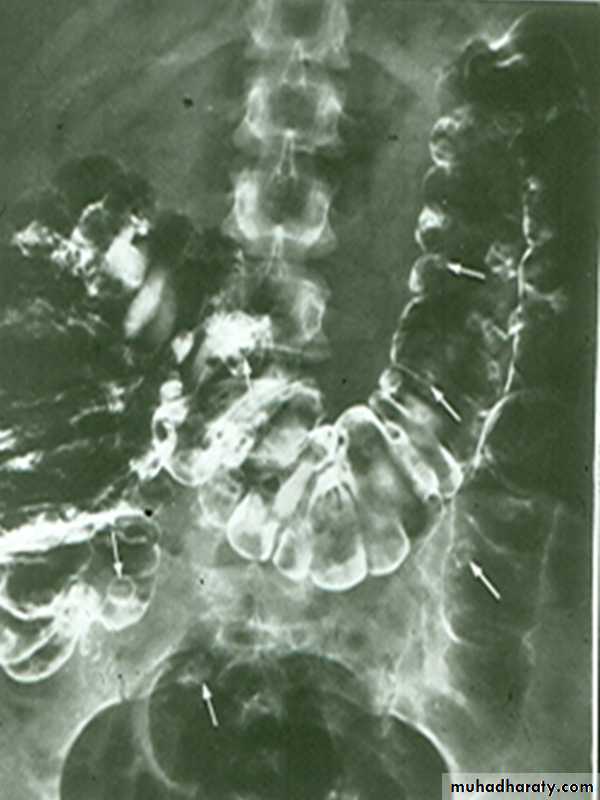

apple core lesion in the descending colon

Multiple lesions are seen in the liver and spleen consistent with metastases

• Morphological types:• 1_ Ulcerative : give rise to irregularity of the colon with ulceration.

• 2_ Constrictive or infiltrative ( Annular ) type :

• a- Constant narrowing .

• b-Shouldering sign, apple core sign .

• c- Destruction of mucosa at narrow area .

• d- Double track due to fistula .

• e- In severe constriction ; stoppage of Ba. Flow with proximal dilatation .